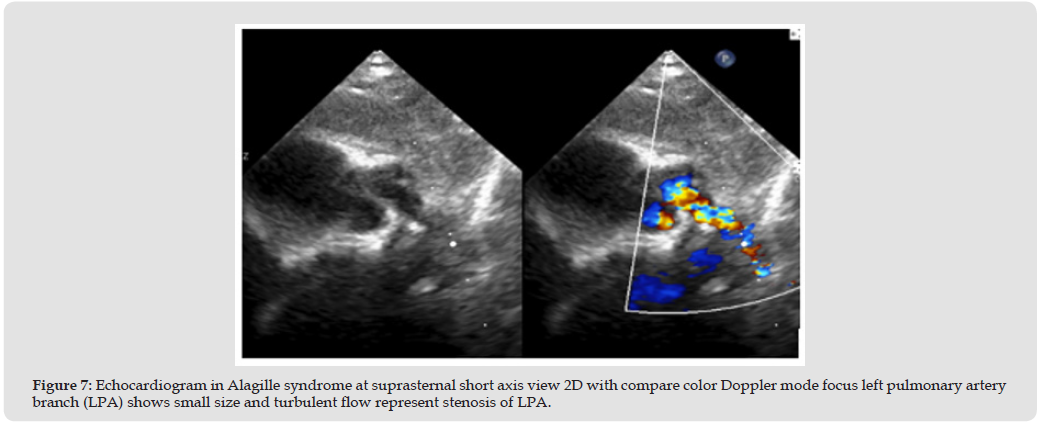

Alagille syndrome have main condition associate with cardiac are right side heart obstruction such as peripheral pulmonary artery stenosis (PPS). PPS was a common problem and cause for check echocardiography, lead to right heart hypertrophy or pressure elevated and relate to cyanotic signs in some case [7] (Figure 5) The remodeling of vascular intima, tunica media and adventitia lead to not progression of pulmonary artery branches size [8] In normal population, the echocardiography uses McGoon ratio for assessing PA size compare with abdominal descending aorta [9] If McGoon ratio = RPA+LPA/DAo has a value greater than 1.5 or 2.0 indicate to good size of the pulmonary artery [10] If z-score less than -2 may be considering pulmonary artery size abnormal or small, and need to measure pressure gradients across of dual branches, main pulmonary artery, and annulus valve of pulmonic if greater than 60 mm Hg May be considered severe stenosis [11,12] (Figure 6) However, the parasternal short axis of aortic valve level view focusing MPA, PV, and PA branches was a necessary view of measure size and PG across due to the direction of blood flow parallel the echo beam. In the children have a suprasternal long and short axis view is necessary window identified pulmonary artery structure, confluence appearance and size. Especially if we keep transducer marker to the left of the patient about 3 o’clock direction posterior angulation, this view able to visuals the first-loba branches of RPA too. (Figures 7 & 8).